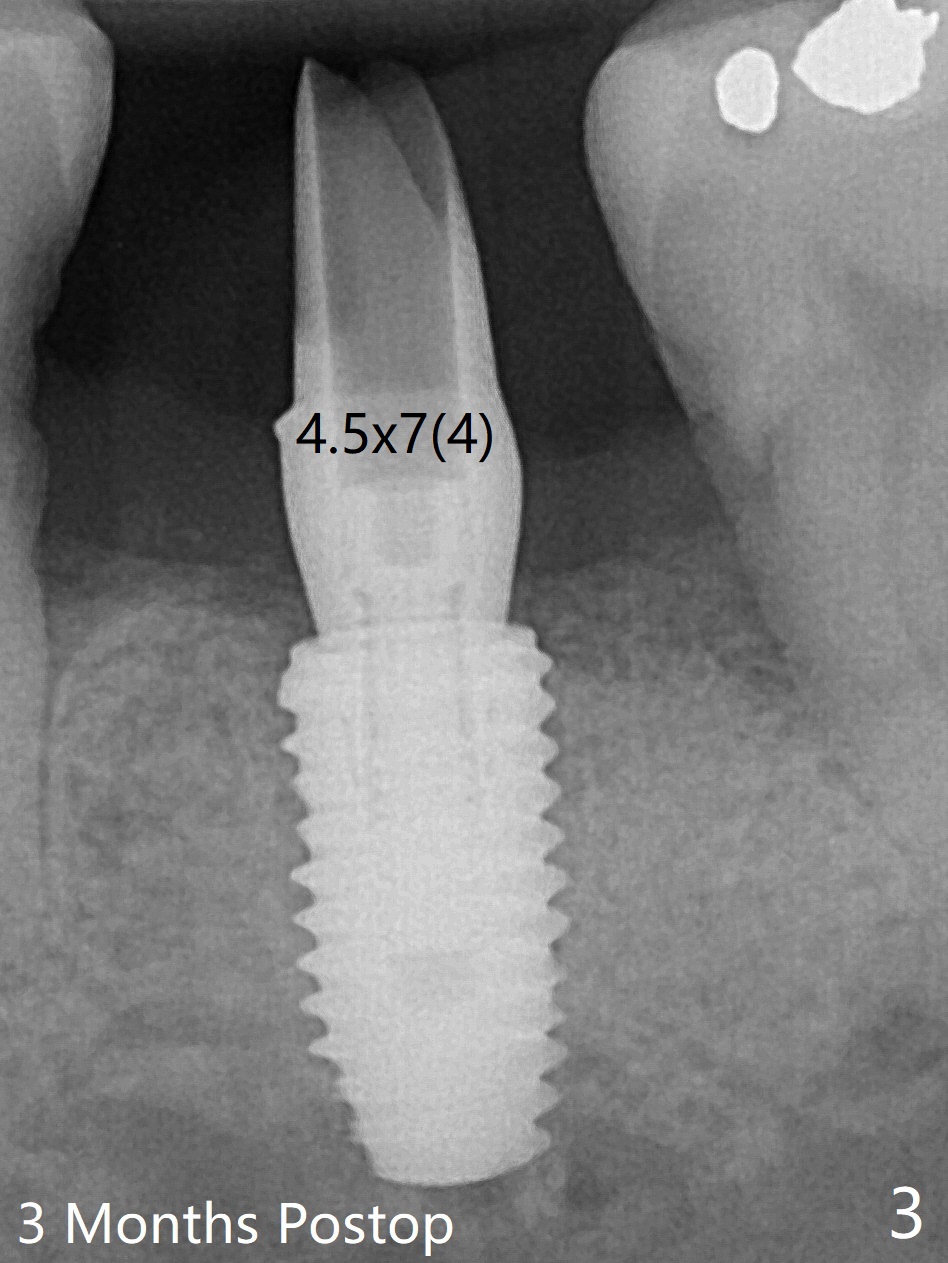

60岁男,吸烟,左下7位点保存后5个月,使用导板环形刀等常规植入5x10毫米IS植体,使用profile drill后,放置6x5毫米愈合基台(图一)。术后3个月,原来近中牙槽窝完全愈合(图二:*),放置5.5x5.7(3)毫米IBS基台,好像没有完全就位,更换4.5x7(4)毫米UF基台就位仿佛改善(图三),降低基台高度后取模。